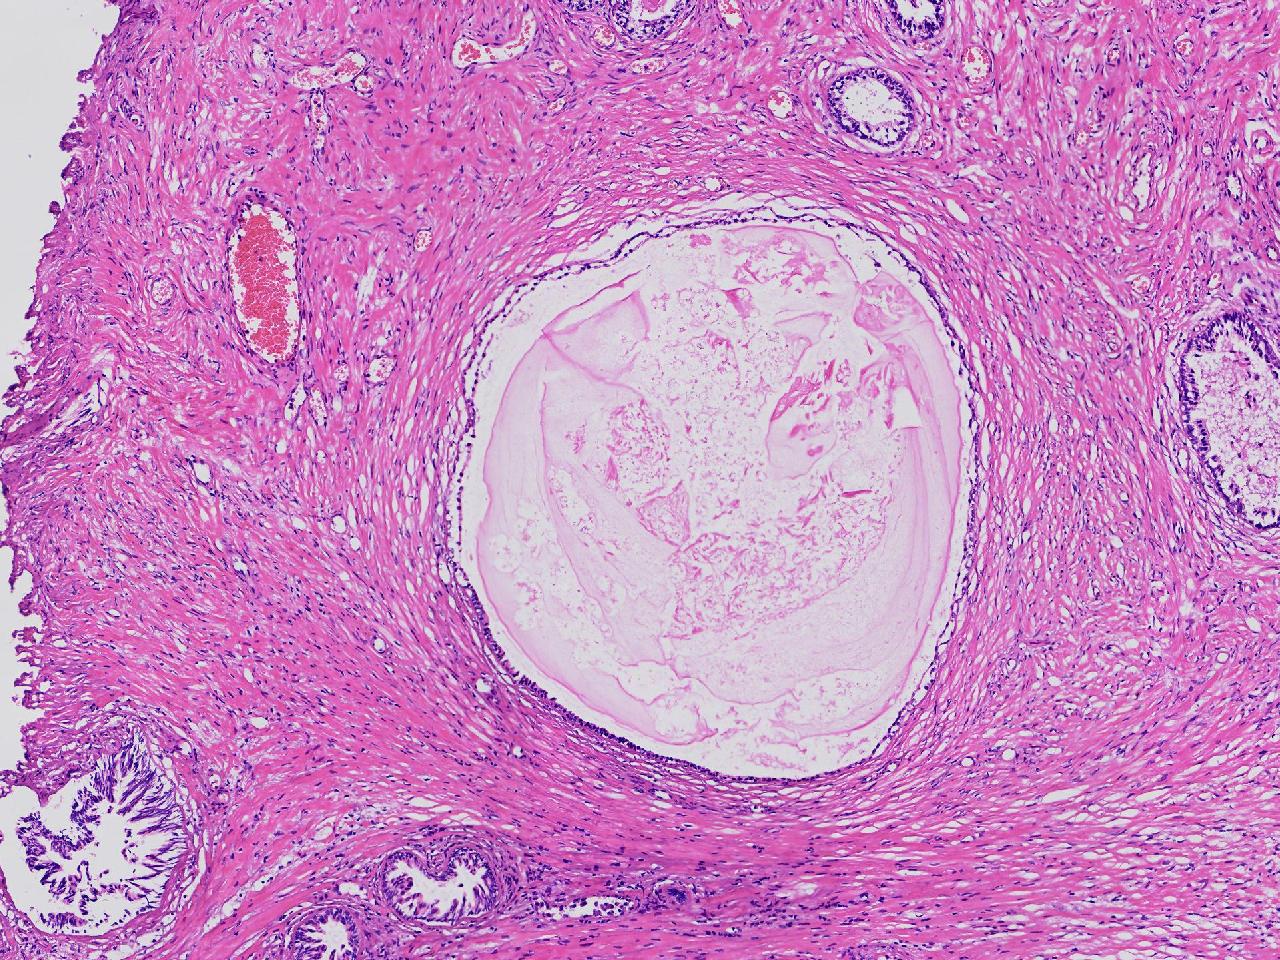

良性前列腺增生?

男,68岁,排尿困难半年余。行前列腺前切术。

前列腺电切标本

灰粉色条索状软组织多块,4X3X3厘米。

考虑为良性前列腺增生症

良性增生

BPH.